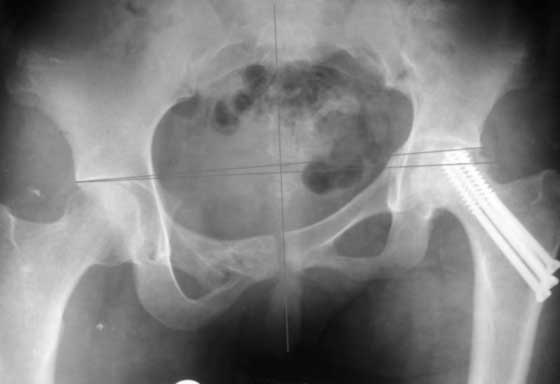

Приветствую! Положительный опыт есть. Первая попавшаяся презентация с похожим сращением.

Многое зависит от деталей видимых после кт и др проекций.

РАВ

В зависимости от данных дополнительных исследований можно предложить операцию - создание опороспобного таза из двух этапов. Остеотомия таза слева через задний доступ на уровне крестцово-подвздошного сочленения и через передний доступ справа на уровне верхней и нижних ветвей лонной кости.

Неплохо было бы провести одномоментную репозицию и фиксацию, но после таких операции благодаря "мягкотканой памяти формы" очень часты осложнении - несостоятельность конструкции.

Двухэтапный вариант имеет преимущества, когда мягкие ткани адаптируются постепенно с помощью того же аппарата внешней фиксации таз-бедро или на скелетном вытяжении.

После достижения желаемого низведения фиксировать "пластиной балкой" сзади, и спереди реконструктивной длинной пластиной, включая симфиз.